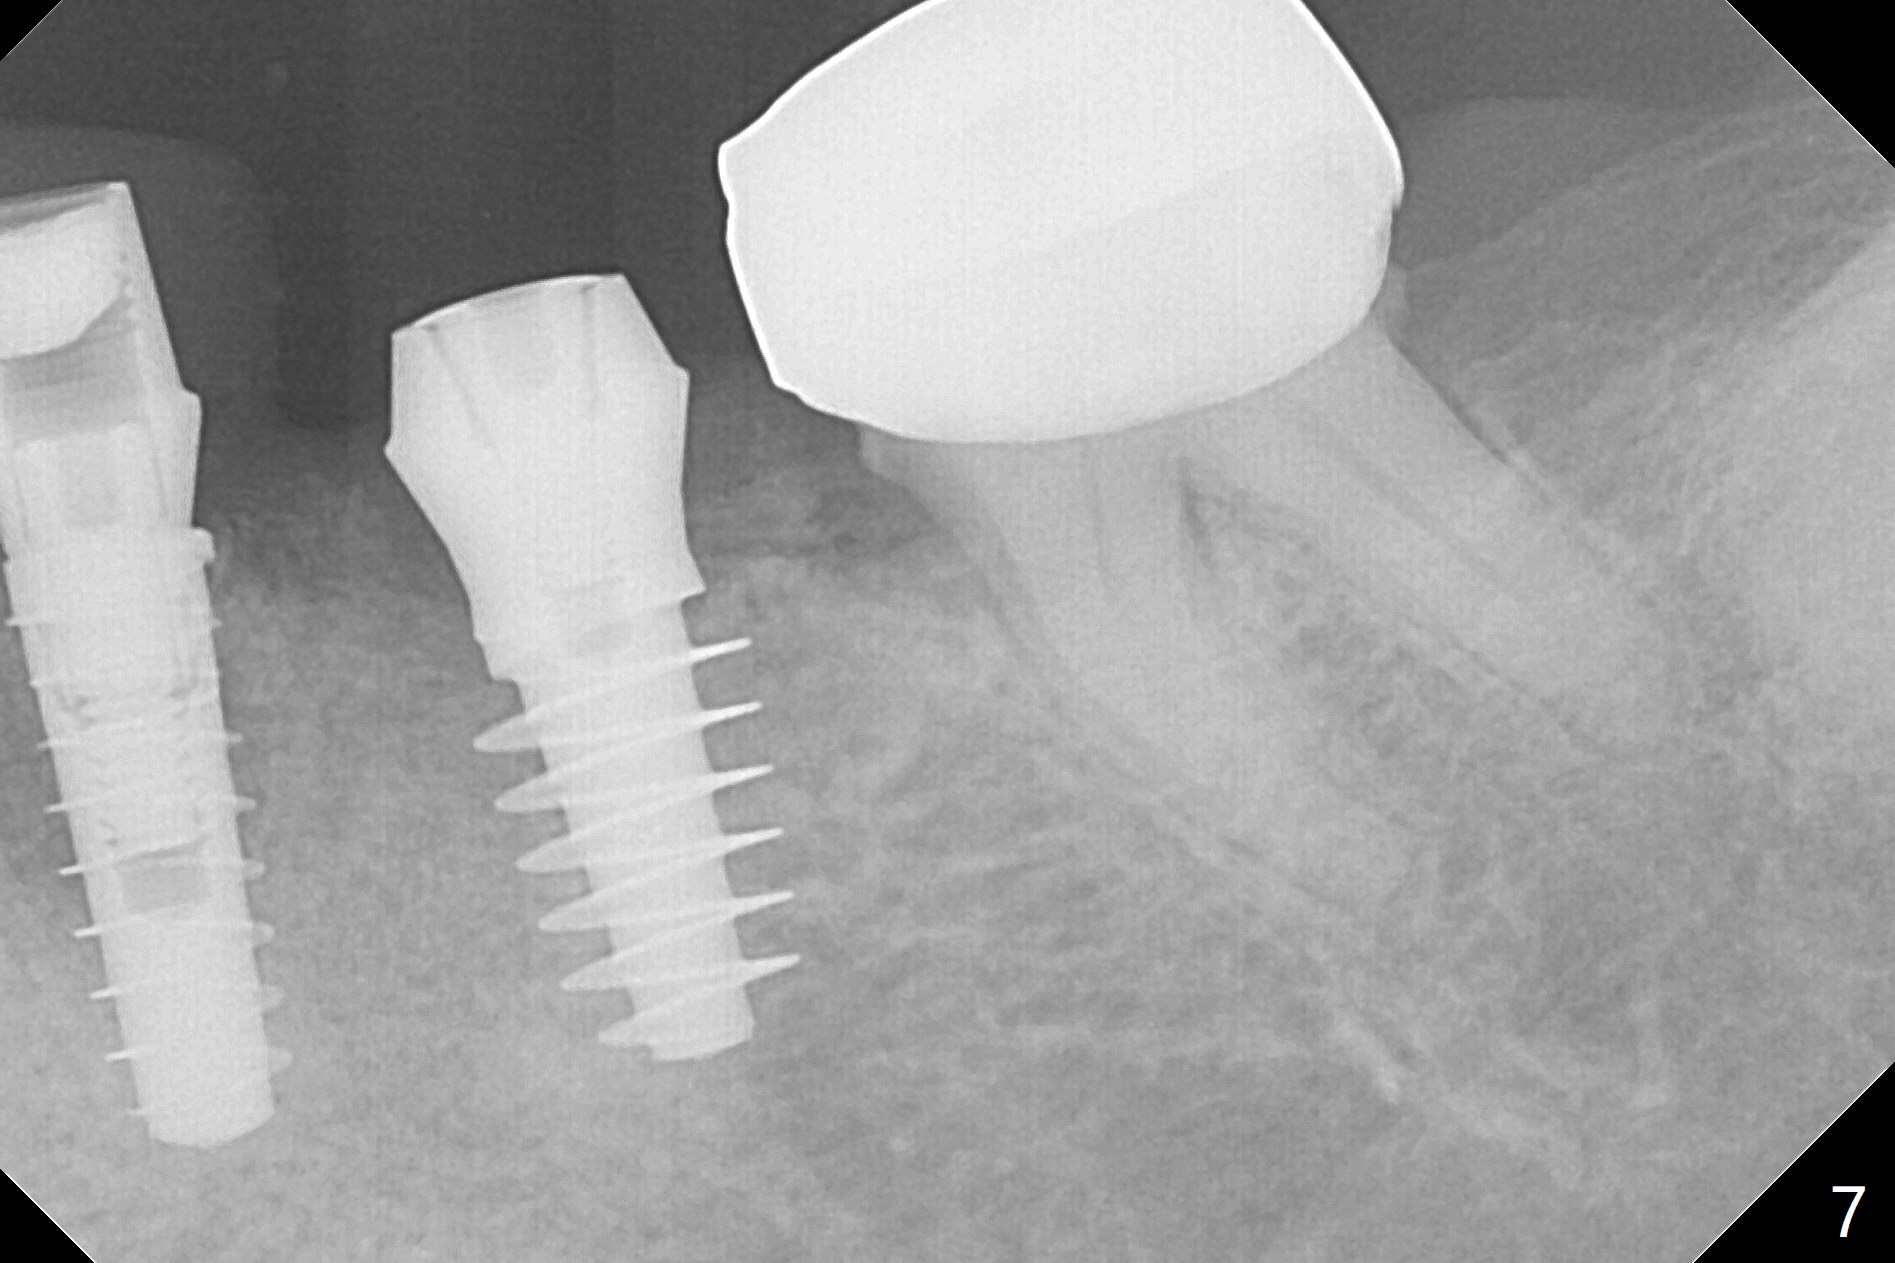

In fact the ridge at #19 is wide (Fig.1); there is enough bone to place a 5 mm implant (Fig.2 (5 mm implant positioner)). The gingiva is 3 mm in thickness. After use of Marking Drill, 5.3 mm Magic Drill (MD) for 9 mm and 4.8 mm MD for ~10 mm, a 5.5x9(3) mm Magicore is placed with primary stability, but too deep. When the implant is reversed, stability loses. After the autogenous bone from bone core is placed in the osteotomy, stability restores to a certain degree (Fig.3); there is no occlusal clearance when a 4.3x3 mm solid abutment is placed. Vera graft is placed around the implant (Fig.4 *) and a healing screw is placed (Fig.4,5).

There is no bone loss at #20 or 19 six and 3 months postop, respectively (Fig.6,7). After placing and trimming a 4.3x3 mm Magicore solid abutment, impression is taken (Fig.8). After cementation for #19 and 20 crowns, the crown of #20 is removed for cement removal; attention is paid to cement removal around the crown at #19. In fact, the removal is ineffective with the crown of #20 is reseated and retightened (Fig.9 >). Repeated removal proves to be futile (Fig.10 >). The most effective method will be to take X-ray immediately after #20 crown removal and reseating without torque so that it will be easier to remove the remaining cement if needed. It may be ok in term of hygiene, since proximal brush is used daily. While the crowns at #18 and 19 are being redone because of food impaction, the tooth #18 needs RCT; the Magicore seems to have no bone loss 4 months post cementation (Fig.11). CBCT shows that the Magicore seems to have been placed in the middle of the crest 7 months post cementation (Fig.12 (B: buccal)). The gingiva at #19 is apparently healthy 8 months post cementation. The crown at #19 is recemented 10.5 months post cementation (Fig.13).